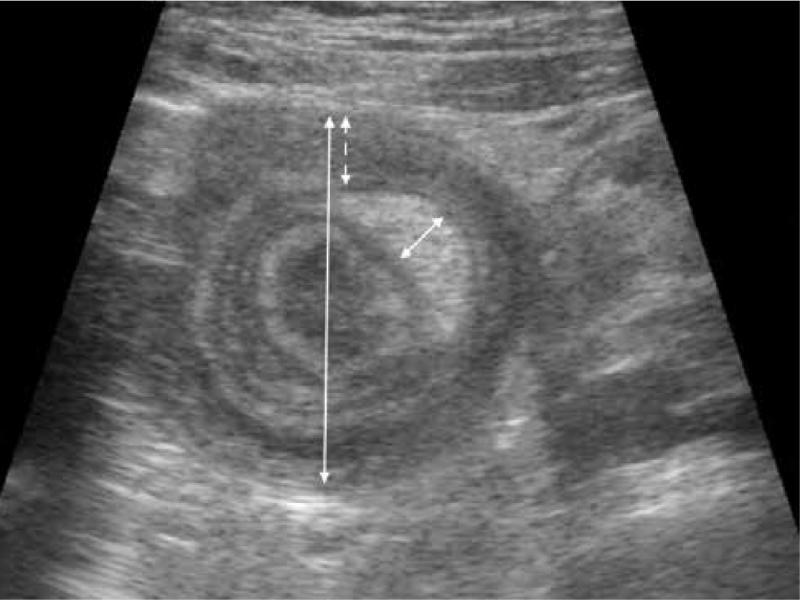

Fig. 2.

Diameter of the lesion – 28 mm (long solid arrow), outer wall diameter – 5.5 mm (dashed arrow) and mesenteric fat core – 4.6 mm (short solid arrow). The fat core-to-outer wall index is 0.84